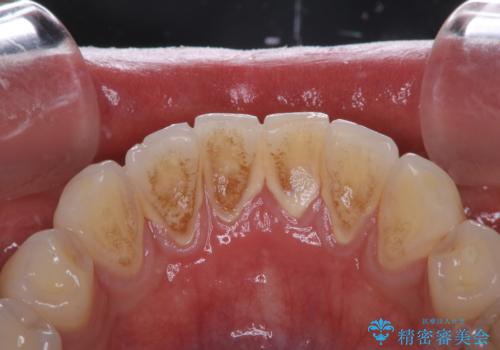

- 歯の色が気になるため、どの処置が適しているか相談してから施術をして欲しいとのことで来院されました。

全体的に汚れが付着していたため、まずはPMTCでご自身の本来の歯の状態にしてから、ホワイトニングにいついて考えましょうとなりました。